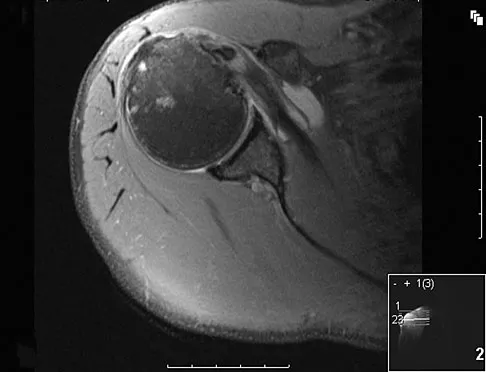

A patient reports persistent anterior shoulder pain following a forceful external rotation injury to the shoulder. An MRI scan is shown in Figure 4. The patient remains symptomatic despite 3 months of nonsurgical management. Treatment should now consist of